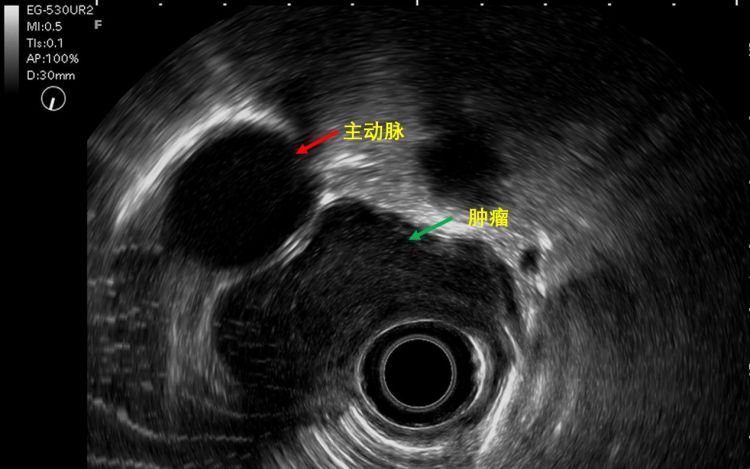

超声内镜是内镜中的望远镜,既有内镜检查的直观性,又有超声检查的穿透性,可以穿透肠壁看到远处,结果显示,可能是平滑肌瘤。随后的CT检查也显示,大概率是良性。

据悉,这个肿物虽然是良性,但很大,长10公分,占据整个食管的三分之一,宽5公分,跨食管壁生长,几乎堵塞食管腔,部分长在腔外,紧邻胸主动脉、主动脉弓和支气管分叉,特别是和主动脉之间只有毫米之隔,术中万一损伤主动脉,分分钟下不了台。